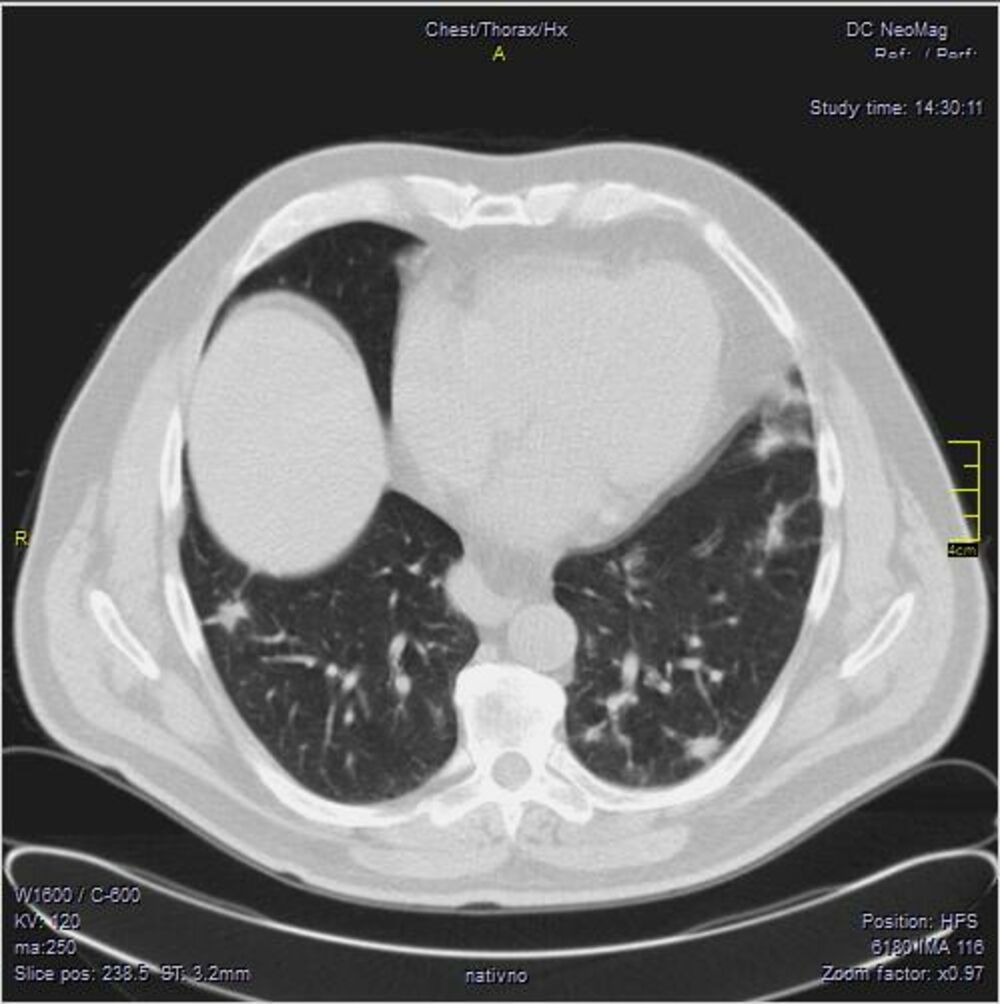

April 2021. Počinju da dolaze pacijenti koji imaju drugačiji nalaz.

Ono što je karakteristično je to da su ovo nalazi koji su 2. i 3. dana bolesti u I fazi. Znači ne u progresivnoj, već u uvodnoj fazi kada uglavnom nema CT znaka. Fibrozne trake već drugog dana???? Ground glass oko većih grana bronha. Kao da bolest ne može da sačeka, kao da klija gde stigne.

Klinička slika se razlikuje od britanskog soja. To se slažu i moji pulmolozi. Za sada je desetak pacijenata (kod mene), malo za zaključke, ali to su pacijenti u kratkom vremenskom periodu od 31.03.2021. godine do 14.04.2021. godine.

Neće mi biti iznenađenje ako se pokaže da već imamo novi soj virusa. Ne mogu da tvrdim da je brazilski, ali se svakako razlikuje.